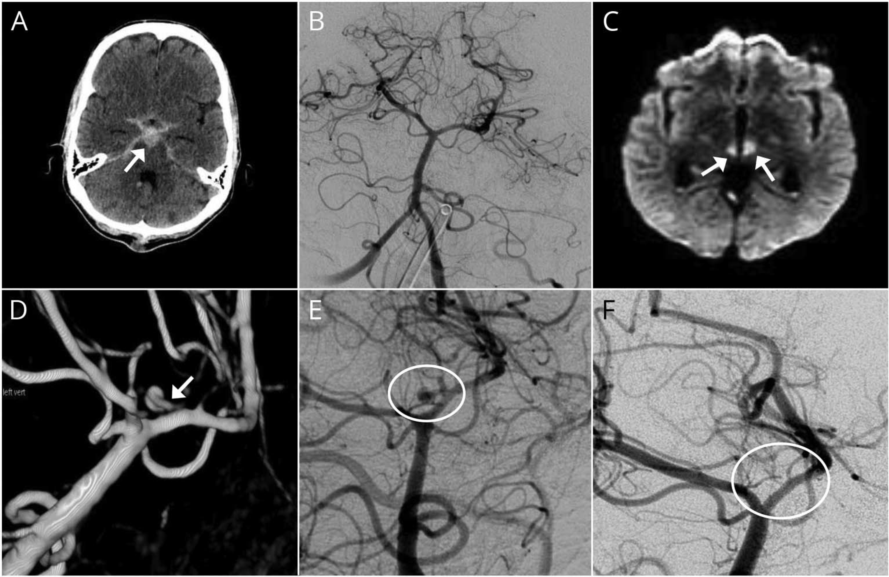

第31批援几内亚中国医疗队成功救治颅内动脉瘤破裂出血患者当地神经外科医生问及佟献增医生为何单凭头颅CT平扫就能够大致判断出血原因和动脉瘤部位时,佟献增医生解释道:自发性蛛网膜下腔出血最常见于颅内动脉瘤破裂,根据外院的头颅CT平扫,双侧大脑前动脉A2段供血区有急性脑梗死,考虑是前交通动脉瘤破裂出血引起双侧大脑前动脉痉...